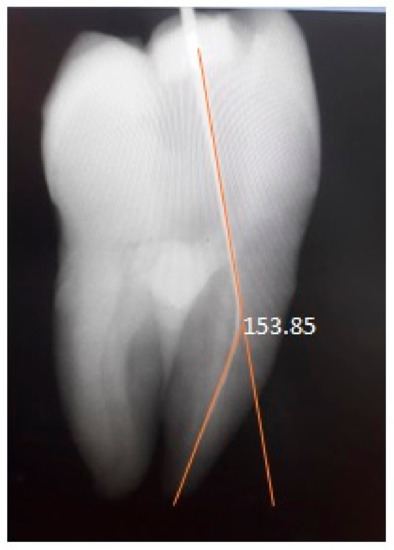

2.3. Determination of Canal Curvature Using Plywood Jig Technique

2.4. Determination of Canal Curvature Using Schneider Technique